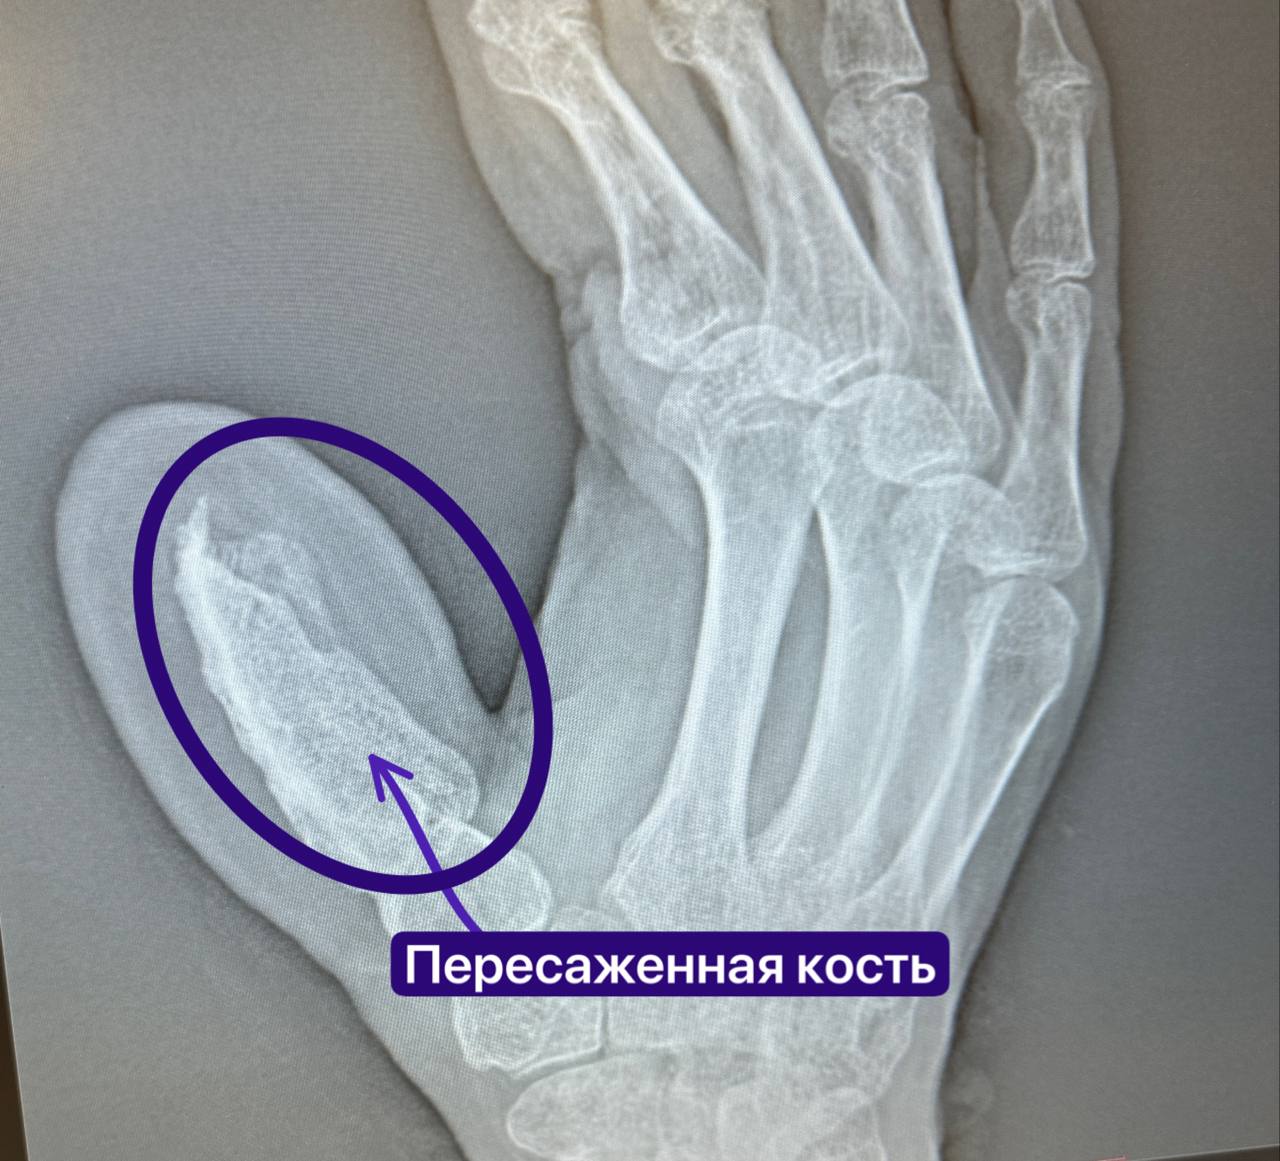

В РКБ Татарстана микрохирурги вырастили челнинцу новый палец

Необычный клинический случай завершился успехом в Республиканской клинической больнице Татарстана. Медики сумели восстановить большой палец руки пациенту, потерявшему его в результате бытовой травмы. Об этом пишет пресс-служба РКБ.

Ключевым этапом стала сложная операция, которую провели опытные хирурги Руслан Тельманович Радьков и Эльвира Рафиковна Кадырова. Они выполнили пересадку костного фрагмента длиной пять сантиметров материал взяли из гребня подвздошной кости, сохранив при этом питающую артерию. Для обеспечения необходимого кровоснабжения временно зафиксировали руку к животу пациента. Четырёхчасовая операция прошла без осложнений.

Полуторамесячный период после вмешательства был критически важен: врачи внимательно наблюдали за процессом приживления трансплантата. Как отмечают специалисты, подобная методика требует от пациента немалой выдержки не все готовы мириться с временными ограничениями. Однако именно такой подход обеспечил полноценное кровоснабжение пересаженной кости, что стало залогом успеха.